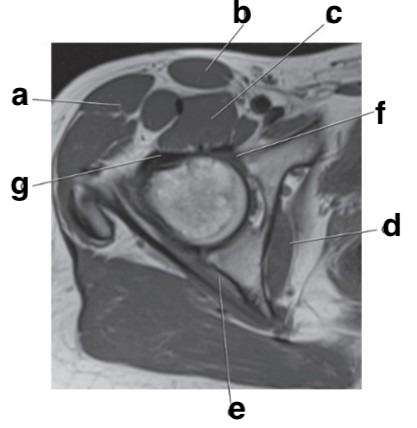

Which letter is the Anterior acetabular labrum?

f

What is letter c?

Superior glenoid labrum

What is letter d?

Posterior glenoid labrum

What imaging plane is this?

coronal

Number 2 is on the __________ side of the patient.

lateral